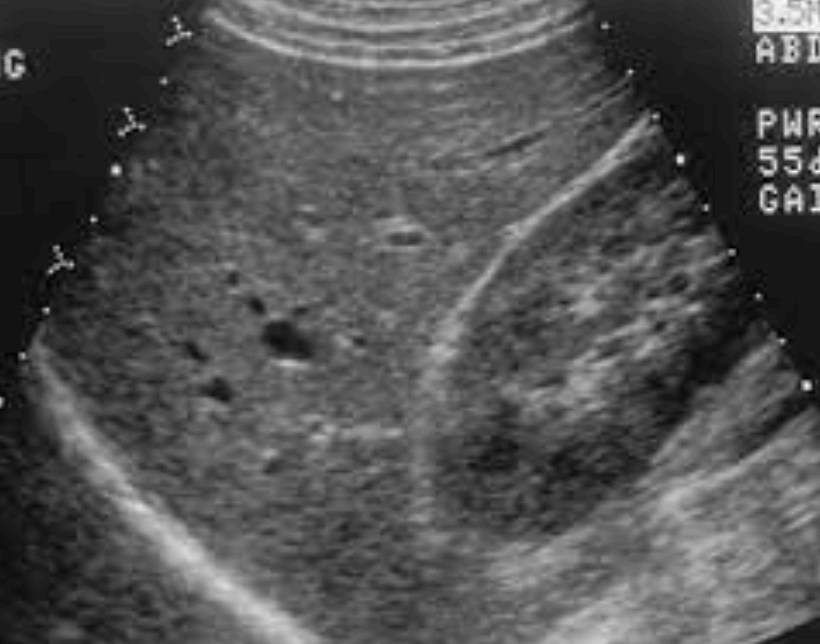

- 간실질의 부종으로 인해 간이 전체적으로 저에코로 나타난다

- 간실질의 불균질 한 에코가 증가한다.

- 문맥 말초지의 묘출 불명료

- 간의 변연이 둔탁해진다